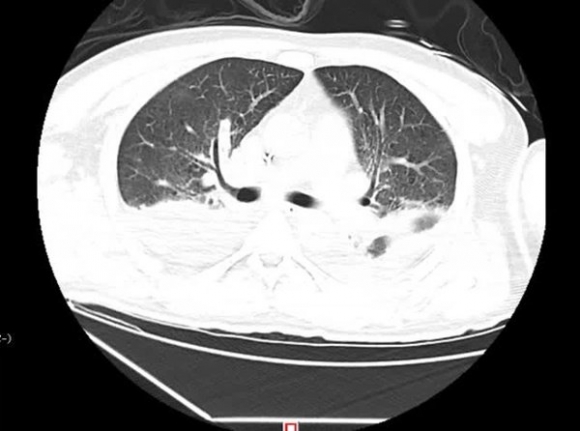

Ngày 16/5, anh Lưu được đưa đến Khoa Cấp cứu tại Bệnh viện Nhân dân tỉnh Hồ Nam (Trung Quốc) trong tình trạng sốt trên 40 độ C. Kết quả kiểm tra CT phát hiện tràn dịch 2 bên ngực, viêm phổi cấp, xét nghiệm máu cho thấy xuất hiện tình trạng giảm oxy máu nghiêm trọng, suy hô hấp, buộc phải thở máy, lập tức chuyển đến phòng cấp cứu đặc biệt (EICU).

Tổn thương phổi do Legionella pneumophila gây ra.